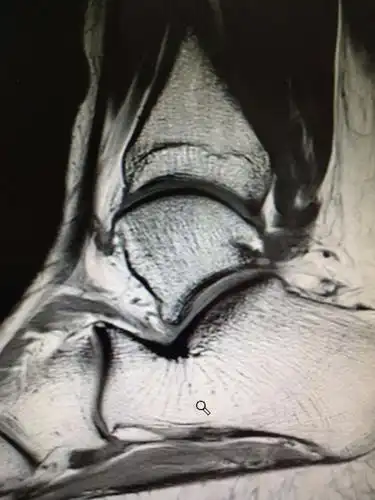

踝关节外侧副韧带损伤合并撕脱骨折的治疗

陈旧外踝韧带撕脱骨折的碎片?